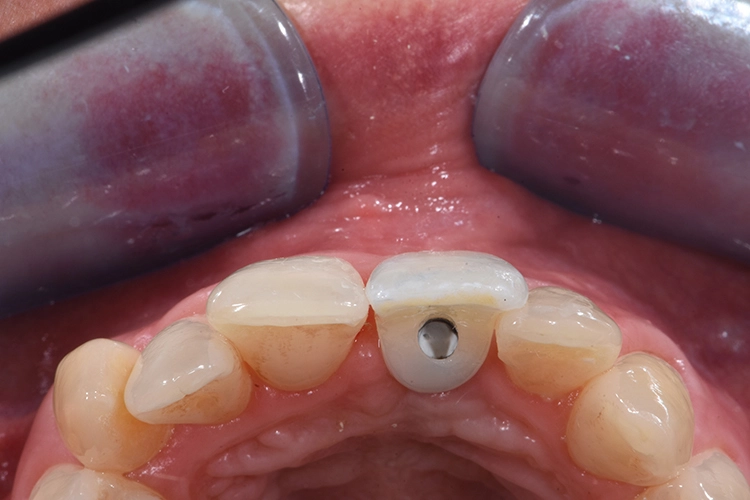

Nach der Lokalanästhesie wurde zunächst ein Kunststoff Jig hergestellt, der die Inzisalkante des Zahnes 11 mit denen der Nachbarzähne verbindet. Dieser dient zur späteren Positionierung der Zahnkrone, wenn diese zum Provisorium umgearbeitet wird und mit dem Implantat verbunden wird. Dieser Schritt ist besonders wichtig, da es für ein unauffälliges postoperatives Ergebnis auf die korrekte Positionierung des Zahnes ankommt und die Positionierungshelfer das Handling und den adhäsiven Verbund unglaublich vereinfacht (Abb. 20 und 21).

Für die Herstellung des Provisoriums wird die Zahnkrone zunächst von Granulationsgewebe befreit, anschließend mithilfe rotierender Instrumente und dem Sandstrahlgerät gereinigt und für die adhäsive Verbindung mit dem PEEK-Aufbau vorbereitet. Intraoral wird die Zahnkrone mit dem provisorischen Abutment verklebt.

Die erste Verbindung dient ausschließlich der dreidimensionalen Fixierung in Relation zum Abutment. Die weitere Ausarbeitung der Krone erfolgt extraoral, wobei auf die Gestaltung eines physiologischen Emergenzprofils geachtet werden muss. Anschließend wird das Provisorium einfach auf die Implantat-Basis geklickt, das Bild zeigt die Situation unmittelbar nach der Implantation (Abb. 23-28).